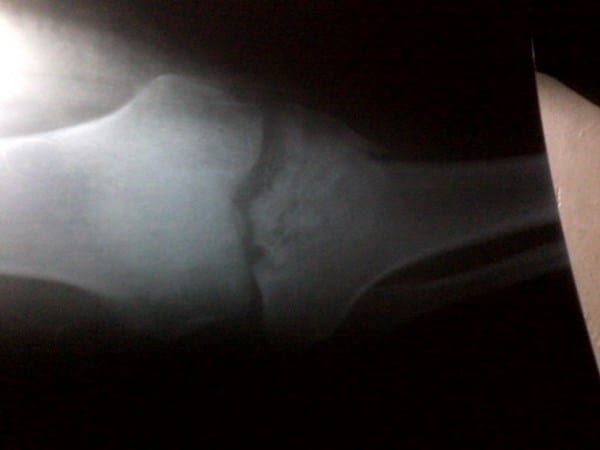

El 01/01/16 tube una accidente en motoxicleta fractura una meseta de la tibia con desplazamiento 2ml y no pude operarme por falta de recursos monetario la mantuve inmovilizada por 3 meses y sin afincarla hace días me tome RX y la meseta tibial ya pego tiene callo quedo un poquito hundida como un 1ml mi pregunta es quedare con dificultades para caminar y puedo ya realizar rehabilitaciones camino con un bastón apenas acá le ajunto la RX reciente gracias y esperando una pronta y positiva repuesta un DIOS LE PAGUE

Como el hueso ya soldó sigue con tu recuperación y usa bastón hasta que veas que puedes afincar sin sentir molestias. No hagas esfuerzos ni abuses, recuerda que lo importante es que esta lesión quede completamente sana, Cuídate y siempre realiza tus actividades con precaución para evitar alguna recaída, Dios no lo permita.